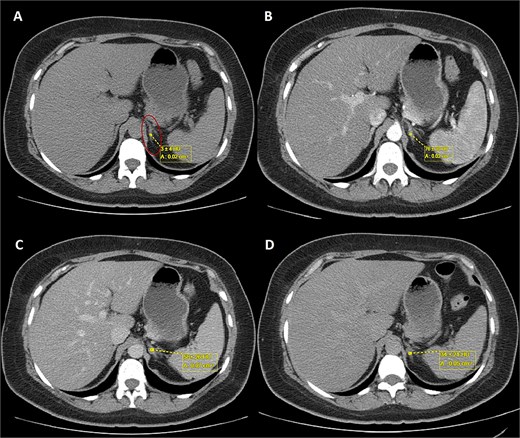

A 44-year-old female patient with a history of abdominoplasty and cesarean section presented with a long-standing history of unexplained headache and nocturnal sweating, accompanied by fatigue and adynamia. The evaluation revealed elevated blood pressure and persistent moderate hypokalemia that did not respond to clinical management. A diagnostic approach was completed to determine the trans tubular potassium gradient (TTKG) and renin/aldosterone ratio (AAR), with elevated values suggesting primary hyperaldosteronism (Fig. 1). An abdominal computed tomography (CT) scan revealed findings compatible with left adrenal adenoma (Fig. 2). A robotic-assisted laparoscopic left adrenalectomy was performed (Fig. 3), finding a left adrenal gland ⁓4 × 4 cm in diameter with a tumor ⁓2 cm in diameter attached to it. The procedure, which lasted 120 min and produced a minimal amount of blood loss of 10 mm, was uneventful. Following successful postoperative progress, the patient was discharged on the second postoperative day.

Triphasic abdominal CT scan with left adrenal adenoma (ellipse). (A) Simple phase, (B) arterial phase, (C) venous phase, (D) late venous phase.

In this case, elevated TTKG and ARR, along with imaging findings [size <4 cm with tumor with regular borders without calcifications, low attenuation <10 Hounsfield Units (HU), high uptake in the arterial phase, lower uptake in the venous phase, and absolute wash-out >60%] (Fig. 2), supported the diagnosis of a left-sided aldosterone-producing adenoma. Surgical resection remains the treatment of choice for unilateral disease, offering a potential cure [9, 10].